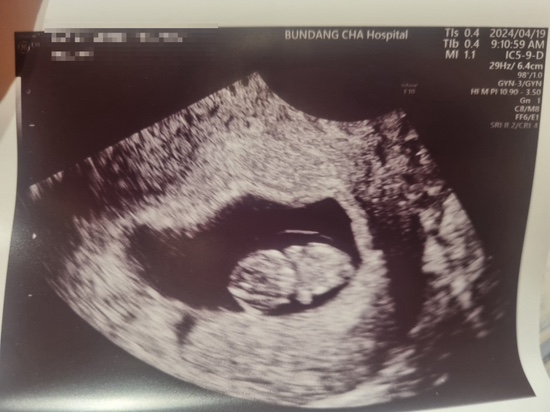

[임신12주]목투병대검사와 산전선별검사

드디어 그 날이 왔다. 아이의 기형여부를 1차적으로 판단할 수 있는 목투명대 검사일. 둘째인 쓰담이는 목...

[임신8주] 귀욤이는 잘 자라나, 아내는 입덧 고생 중

운이 좋게 시험관 1차례 시도로 자리를 잘 잡아준 귀욤이. (귀욤이는 토닥이가 지어준 이름) 8주차에 2.4cm...